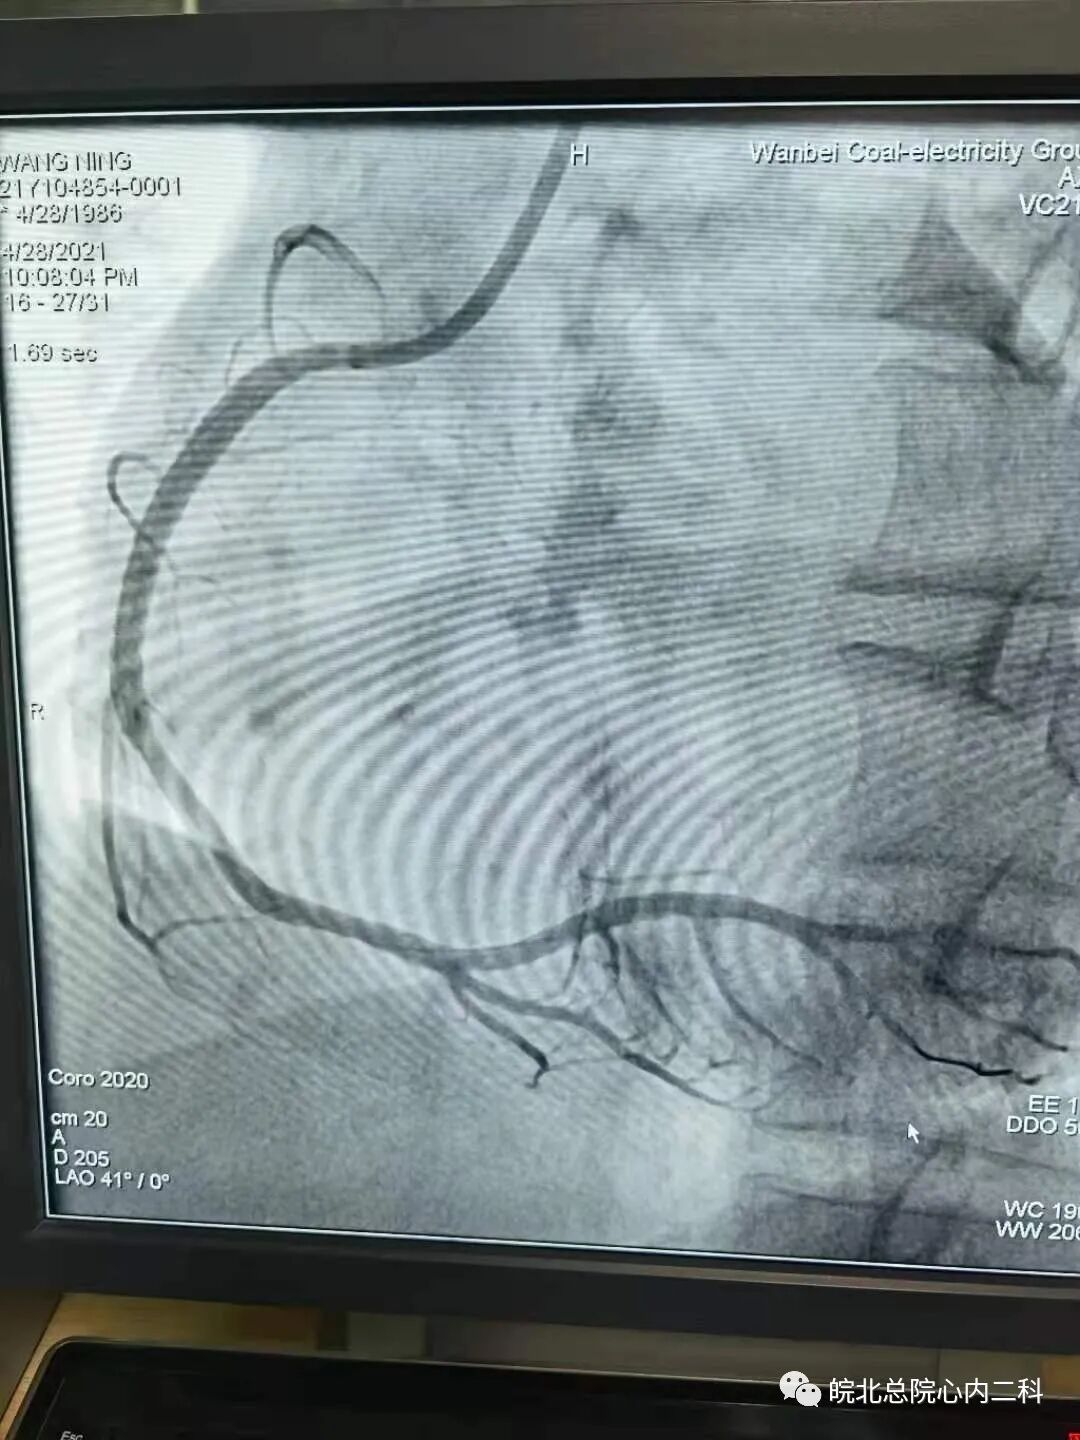

昨日皖北总院心内二科连续抢救两名急性下壁ST段抬高型心肌梗死患者,两名患者均以最短的时间接受了急诊介入治疗,其中一名患者35岁,打篮球后突发胸痛1小时入院,患者直接绕行病房,急诊冠脉造影右冠近中段完全闭塞。崔主任手术团队十分钟导丝通过开通血管,最快的挽救患者的存活心肌,改善患者的预后!目前两位患者生命体征尚平稳,近期可康复出院!